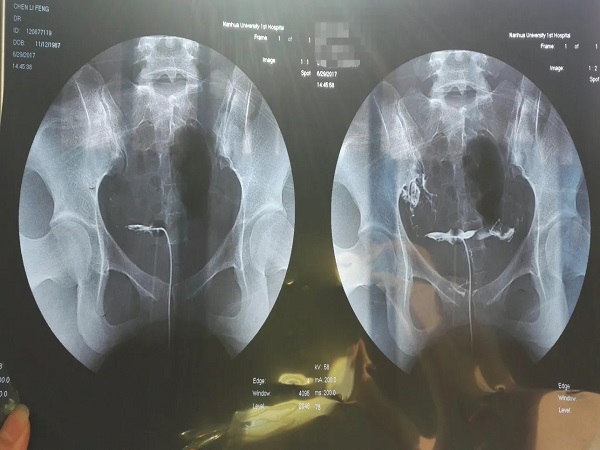

输卵管造影才是最准确的检查方法

综上所述,检查输卵管是否通畅只能够通过做输卵管造影来确定,通过造影剂的流向就能够了解到女性的输卵管是否存在堵塞,如果有堵塞也能够明确知道具体的堵塞部位和程度,方便进行进一步的治疗。总而言之,建议大家最好是通过科学的方法来检测输卵管的情况,以免错过最佳的生育时间。